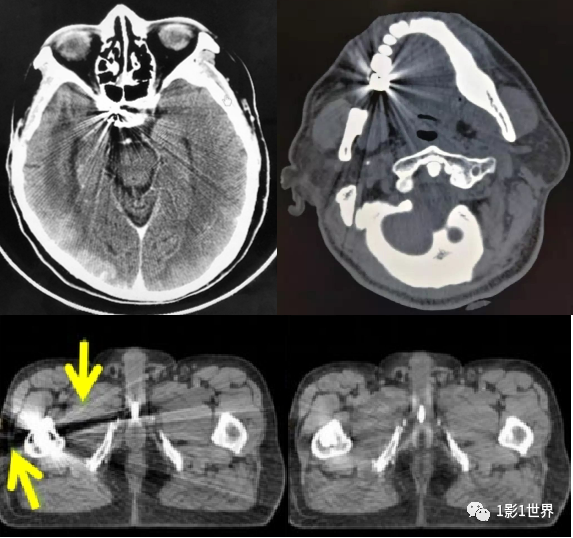

类似硬膜下血肿的运动伪影

就伪影形成的原因,有设备本身因素,有扫描条件设置因素,有患者因素。正面,展示几种临床上常见的伪影,并分析其形成的原理,克服的办法。规范预热;定期空气校准;维护和保养;检测硬件故障,并更换。也叫条纹状伪影,表现为图像上低密直线,无规律出现。插值算法是导致这类伪影的主要原因。伪影的面积比,要随螺距的增大而增大。致密物体之间的条纹状低密度影;如头部后颅窝亨氏暗区,就是典型的更化束伪影。密度相差较大的物体之间的条带状高低密度影;如胃内气体较多时,肝胃之间的伪影。薄层扫描,厚层重建;改变体位